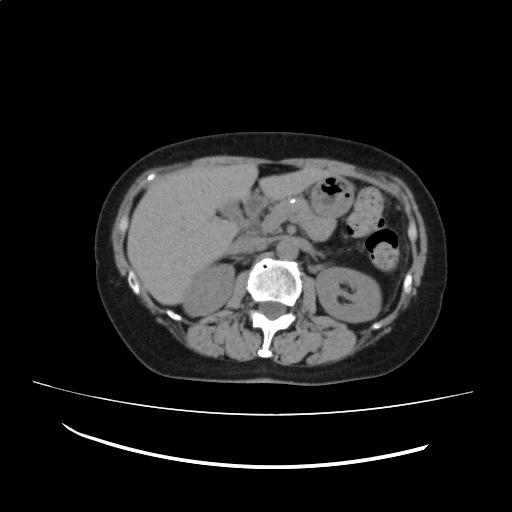

肝内に明らかな占拠性病変(SOL)を認めない。

膵体部に石灰化を認める。主膵管の拡張は認めない。

脾臓に小低吸収域(LDA)を認め、脾門部脂肪と考える。前回と比較して著変なし。

(Impression)

前回検査と比較して著変はない。

CT画像144

(142/198)